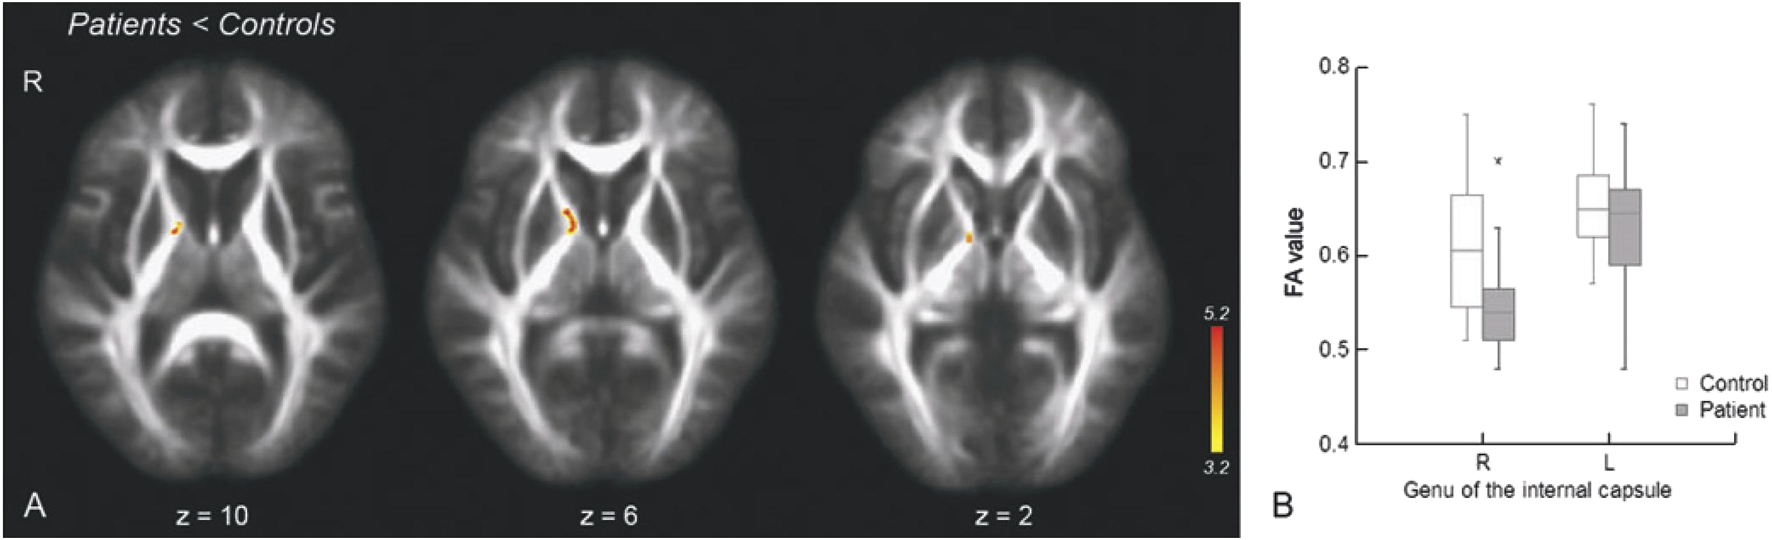

FIGURE 2

Fractional anisotropy in LD compared to controls. (A) Unbiased whole-brain tract-based spatial statistics (color bar indicates the significance range at Z > 3.2). (B)a priori ROI analyses from right genu of the internal capsule (Box plots indicate median and upper and lower quartiles. Error bars indicate the range between the 90th and 10th percentiles. Asterisk indicates significant difference between two groups. R = right; L = left). Reproduced with permission from [50].